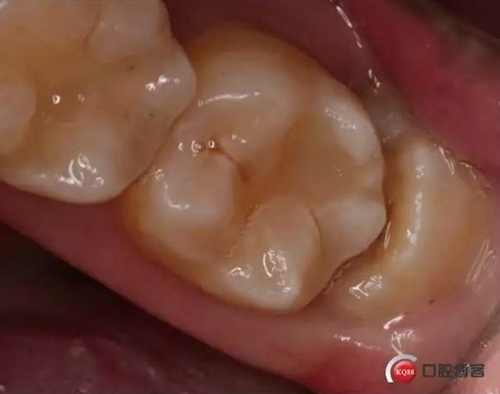

檢查:口內(nèi)可見38未完全萌出,無松動,周圍牙齦顏色正常,叩診(—)觸診(—),X線顯示近中阻生,雙根

處理:治療計(jì)劃及費(fèi)用已說明,知情同意后,排除拔牙禁忌癥:口腔黏膜消毒,左下頜阻滯麻醉成功后,切開翻瓣,渦輪機(jī)去除近中阻力,向近中挺出患牙,拼對牙體完整,清創(chuàng),置明膠海綿,縫合傷口,咬棉球壓迫止血